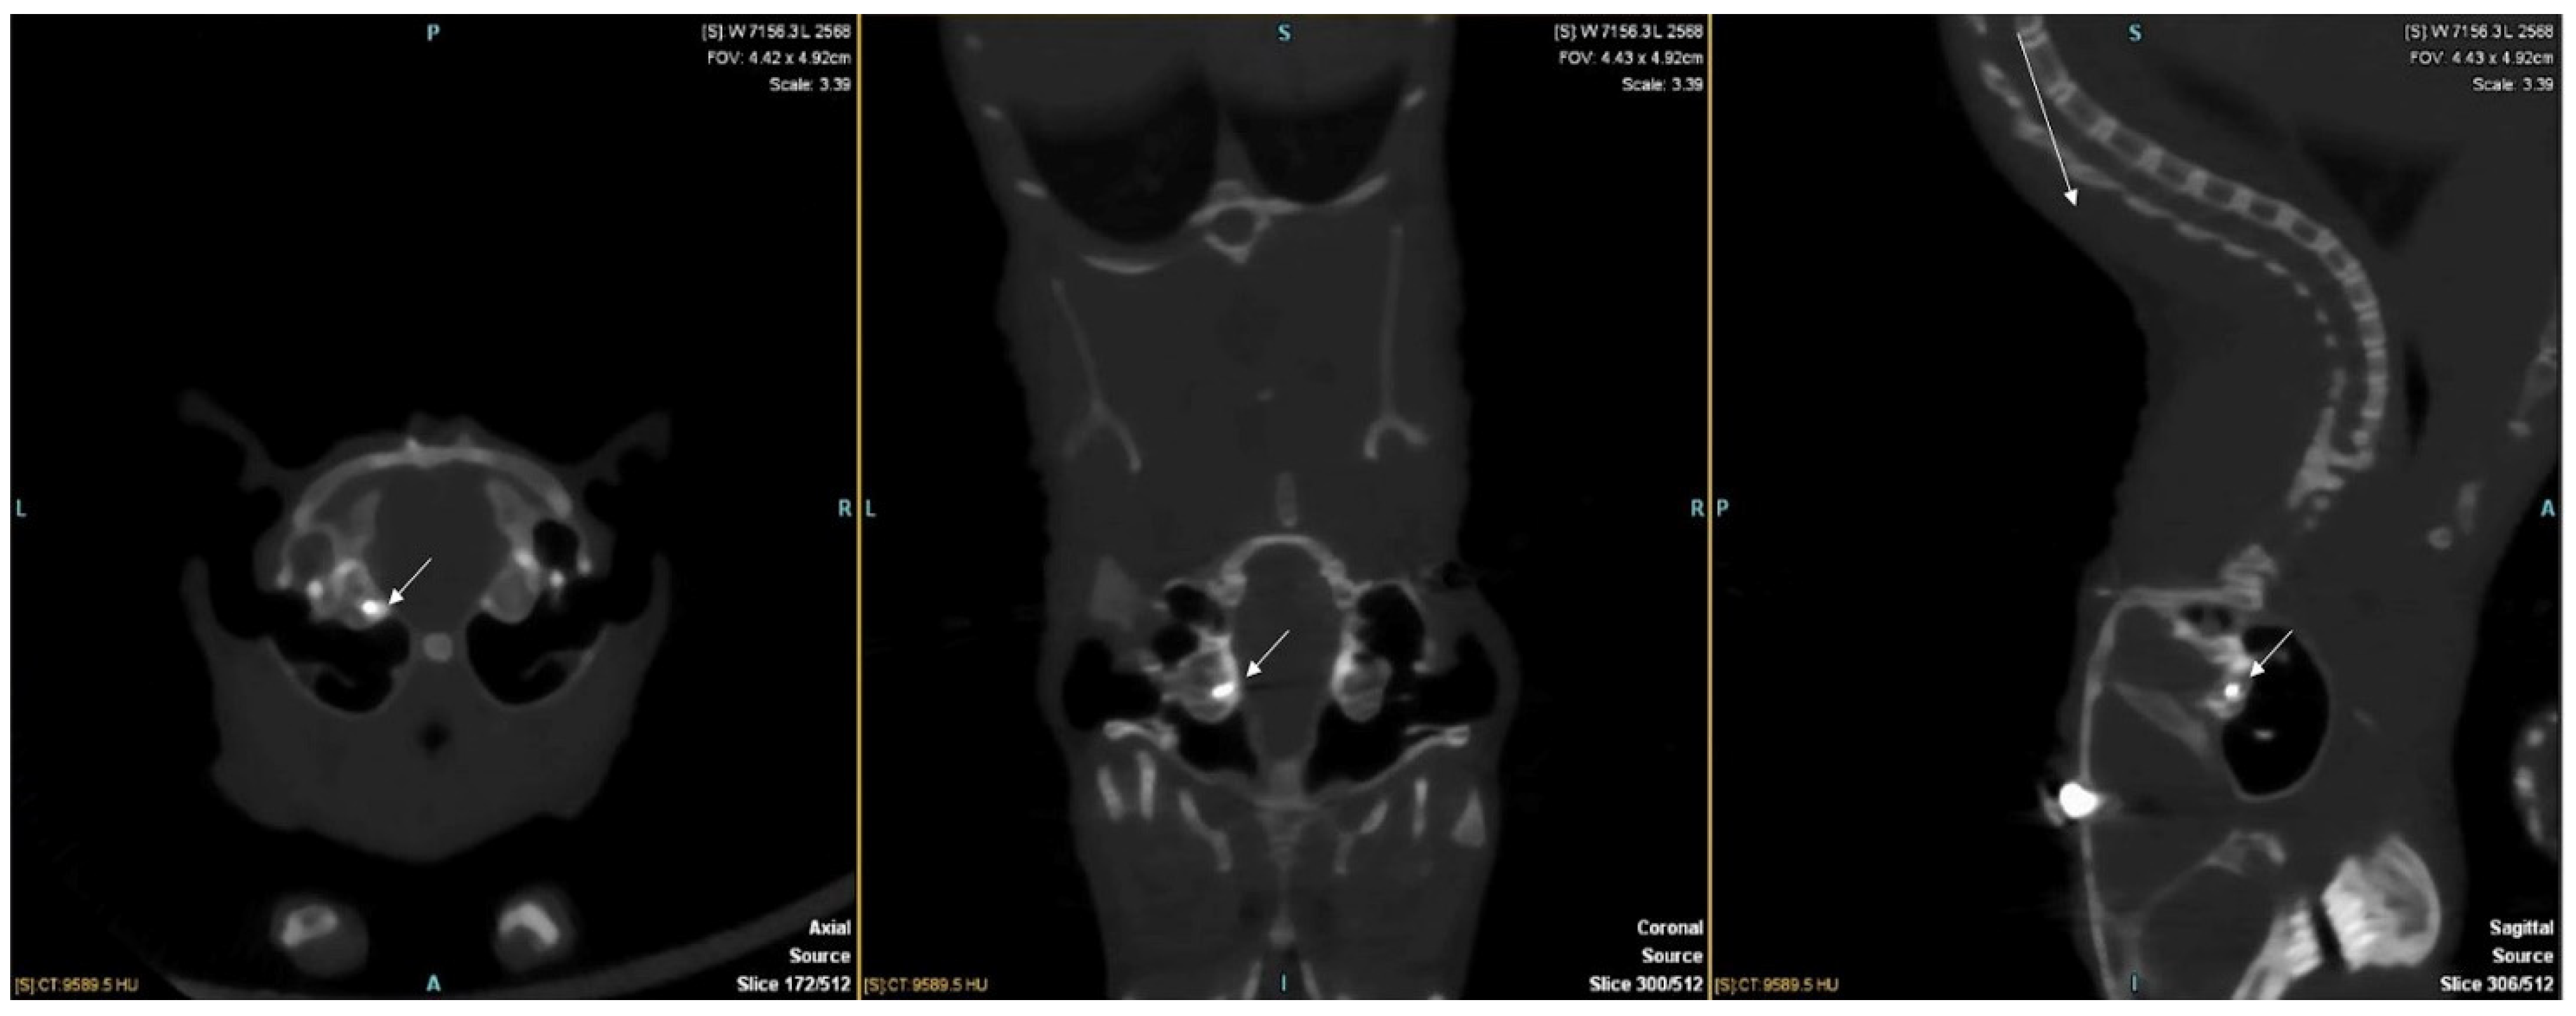

2.2. Cochlear Implant Surgery

2.3. Tissue Preparation

2.4. Light-Sheet Microscopy